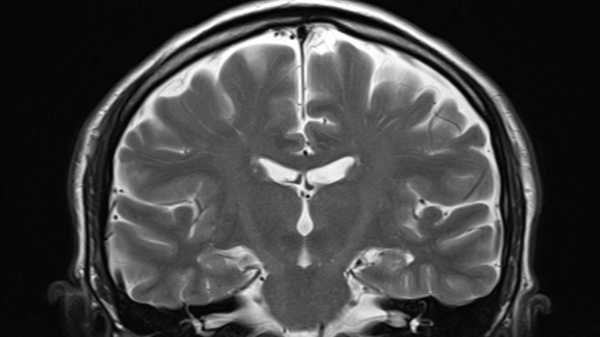

Тим часом, годинник DunedinPACNI базується на даних про структуру мозку, отриманих за допомогою МРТ. Деякі годинники є органоспецифічними, деякі – клітинно-специфічними, а деякі поєднують інші годинники для створення «мультиомних» годинників старіння.

Сканування мозку може розкрити ваш справжній біологічний вік